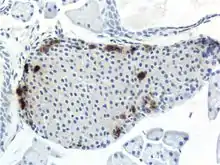

- A pancreatic islet, stained.

- A pancreatic islet, showing alpha cells

- A pancreatic islet, showing beta cells.